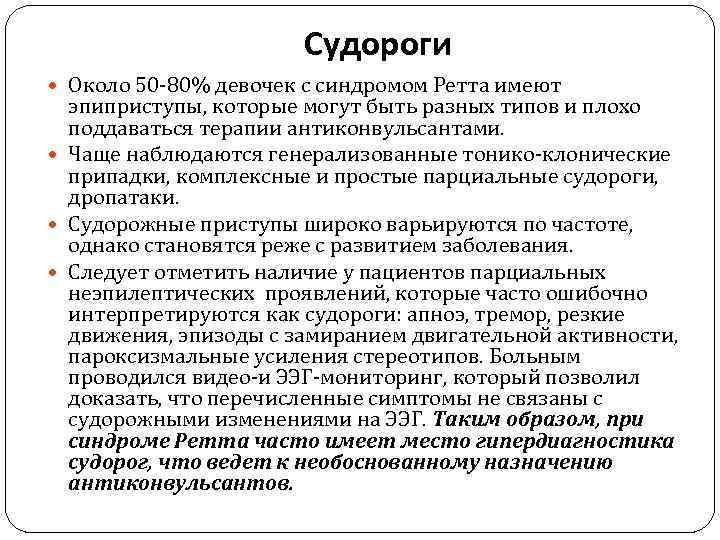

Судороги Около 50 -80% девочек с синдромом Ретта имеют эпиприступы, которые могут быть разных типов и плохо поддаваться терапии антиконвульсантами. Чаще наблюдаются генерализованные тонико-клонические припадки, комплексные и простые парциальные судороги, дропатаки. Судорожные приступы широко варьируются по частоте, однако становятся реже с развитием заболевания. Следует отметить наличие у пациентов парциальных неэпилептических проявлений, которые часто ошибочно интерпретируются как судороги: апноэ, тремор, резкие движения, эпизоды с замиранием двигательной активности, пароксизмальные усиления стереотипов. Больным проводился видео-и ЭЭГ-мониторинг, который позволил доказать, что перечисленные симптомы не связаны с судорожными изменениями на ЭЭГ. Таким образом, при синдроме Ретта часто имеет место гипердиагностика судорог, что ведет к необоснованному назначению антиконвульсантов.